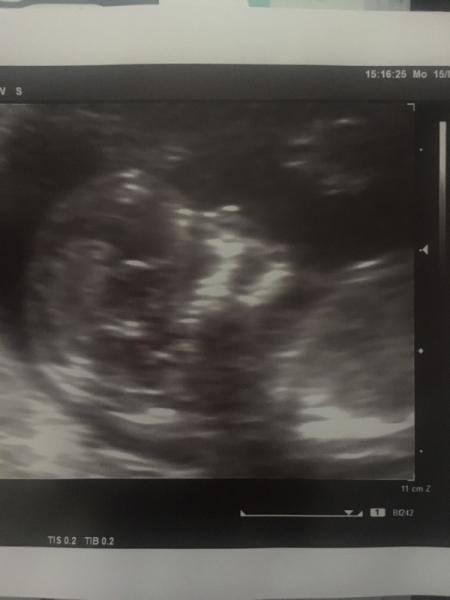

Hatte heute endlich wieder Gyntermin bin heute 12+5 das Krümelchen ist 7 cm (Schädel-Steiß) und gezappelt wie ein wilder hat es glaube es wird genauso hyperaktiv wie mein Freund, war richtig gerührt und happy, ich liebe das kleine einfach schon so arg, unbeschreiblich Leider gehts mir von Übelkeit und Erbrechen nicht viel besser. Habe wieder 2 kg abgenommen und habe insgesamt 7kg unten. Hab jetzt auch die Hyperemesis diagnostiziert bekommen, aber das bedeutet erstmal aussitzen. Zum Glück hab ich eine super Hebamme die alles versucht, dass es mir bald besser geht Hier noch ein Bildchen vom Kopf

Bild zu Das Krümelchen wieder gesehen - Forum für Januar - Mamis

Kopf hoch, du bist nicht allein Hab mich auch schon damit abgefunden, dass ich’s wohl bis in den Kreißsaal hab Ich finde am Tag wo der Ultraschalltermin ist, gehts immer Süß, dass man bei dir so schön das Köpfchen sieht